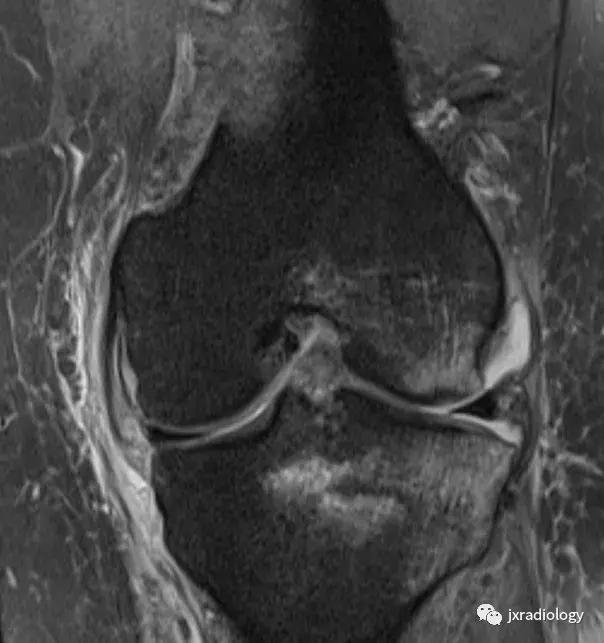

图8:创伤性骨髓水肿,髌骨脱位的典型病例:青年人,髌骨一过性脱位和挫伤的横断面(a,b,c),冠状面(d,e)和矢状面(f)的PD-FS-WI图像 :股骨外侧髁的前外侧和髌骨下内侧的故事水肿。针对进行运动的青少年或年轻人来说,在弯曲时需要膝盖扭转运动的情况更为常见。如该患者患有髌骨骨软骨损伤(*)和内侧髌股韧带(MPFL)撕裂(箭头)。